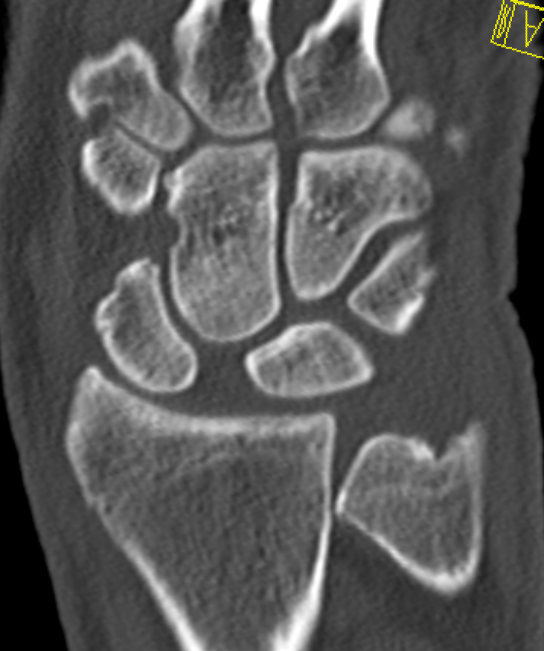

CT

MRI

SL ligament injury with minimal disassociation / SL separation / dynamic instability

SL ligament injury with SL separation and static instability

Increased scapholunate angle